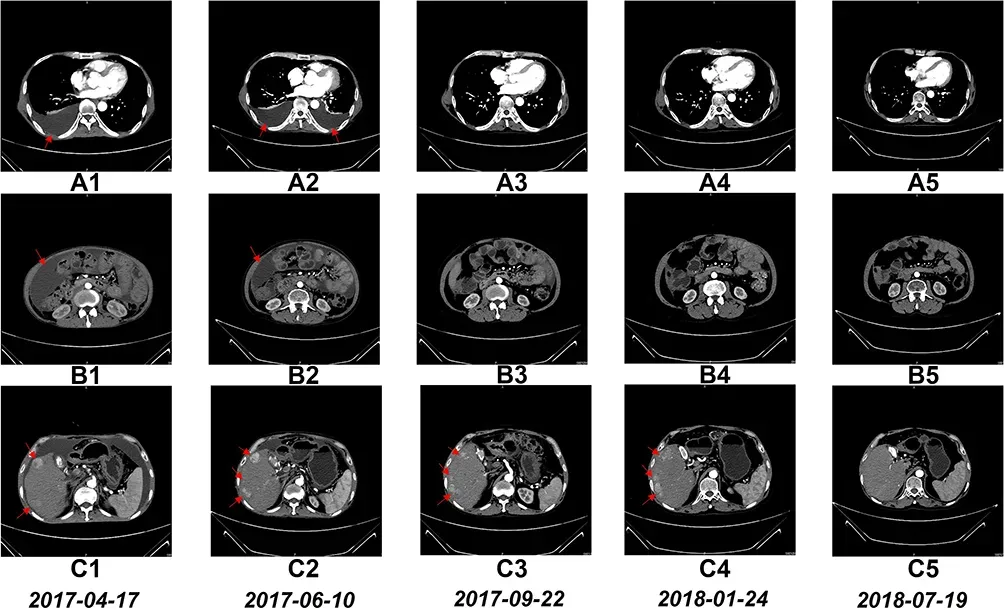

《Oncotargets and Therapy》期刊曾报道了一例晚期肝细胞癌患者的临床案例,该患者在接受近150亿NK细胞输注治疗后,成功实现了带瘤生存超过1400天的显著疗效。

然而,经过TACE和化疗后,患者的肿瘤并未明显缩小,反而因化疗导致身体状况急剧恶化。于是,在2017年3月至2018年7月期间,患者开始接受NK细胞治疗,总共输注了近150亿NK细胞。治疗采取每月一次、连续两天输注的方案,并且在NK细胞治疗期间,患者未接受其他任何治疗。

CT扫描结果进一步证实了治疗效果。6个疗程后,患者的胸水和腹水明显减少,并自此一直保持这种状态。由于患者多次重复治疗周期以巩固疗效,其治疗效果尤为显著。

经过1年4个月的NK细胞治疗后,患者右肝叶中的多个肿瘤大小明显减小。后续数据更显示,该患者的生存时间超过了48个月,即实现了带瘤生存超过4年,近1400天。